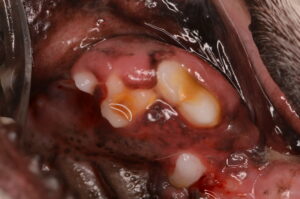

上の画像は歯肉過形成により歯の大部分が歯肉に覆われています。

良性の変化ですが、放置すると歯周病の進行や、歯のトラブルを引き起こす原因になります。